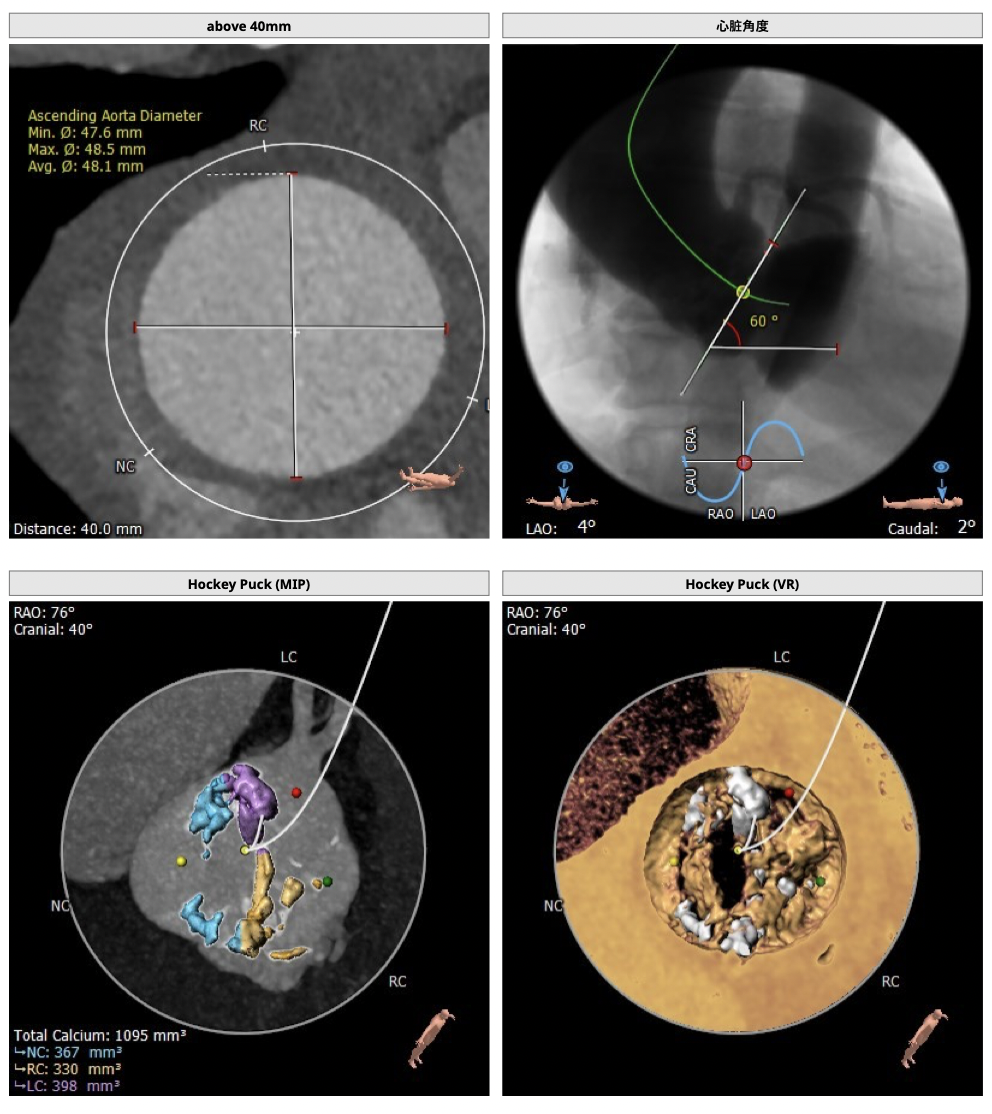

*患者为TYPE1型二叶瓣,左右融合,重度钙化,融合脊难以推开,瓣膜释放后具有一定瓣周漏风险;

*心脏角度为60°,横位心,输送器过瓣难度增加,瓣膜植入同轴性差,瓣膜释放更易移位,增加了操作的难度;

FEops评估报告

FEops评估瓣周漏

根据FEops量化评估,选用L26瓣膜高位释放会导致8.2ml/s的瓣周漏,而选用L26标准位释放会导致7.4ml/s的瓣周漏,两种释放位置产生的瓣周漏均低于发生中度至重度瓣周漏临界值16ml/s,所以两种释放位置均可以纳入考虑范围,由FEops模拟瓣周漏的3D建模得知发生瓣周漏的主要区域为左右交界处的钙化位置。

FEops评估瓣膜稳定情况

根据FEops评估的L26瓣膜标准位释放结果,发现瓣膜起始位置与稳定位置有较大的改变,判断发生下滑可能性比较大,建议使用VenusA-Plus®可回收输送系统保障手术安全。